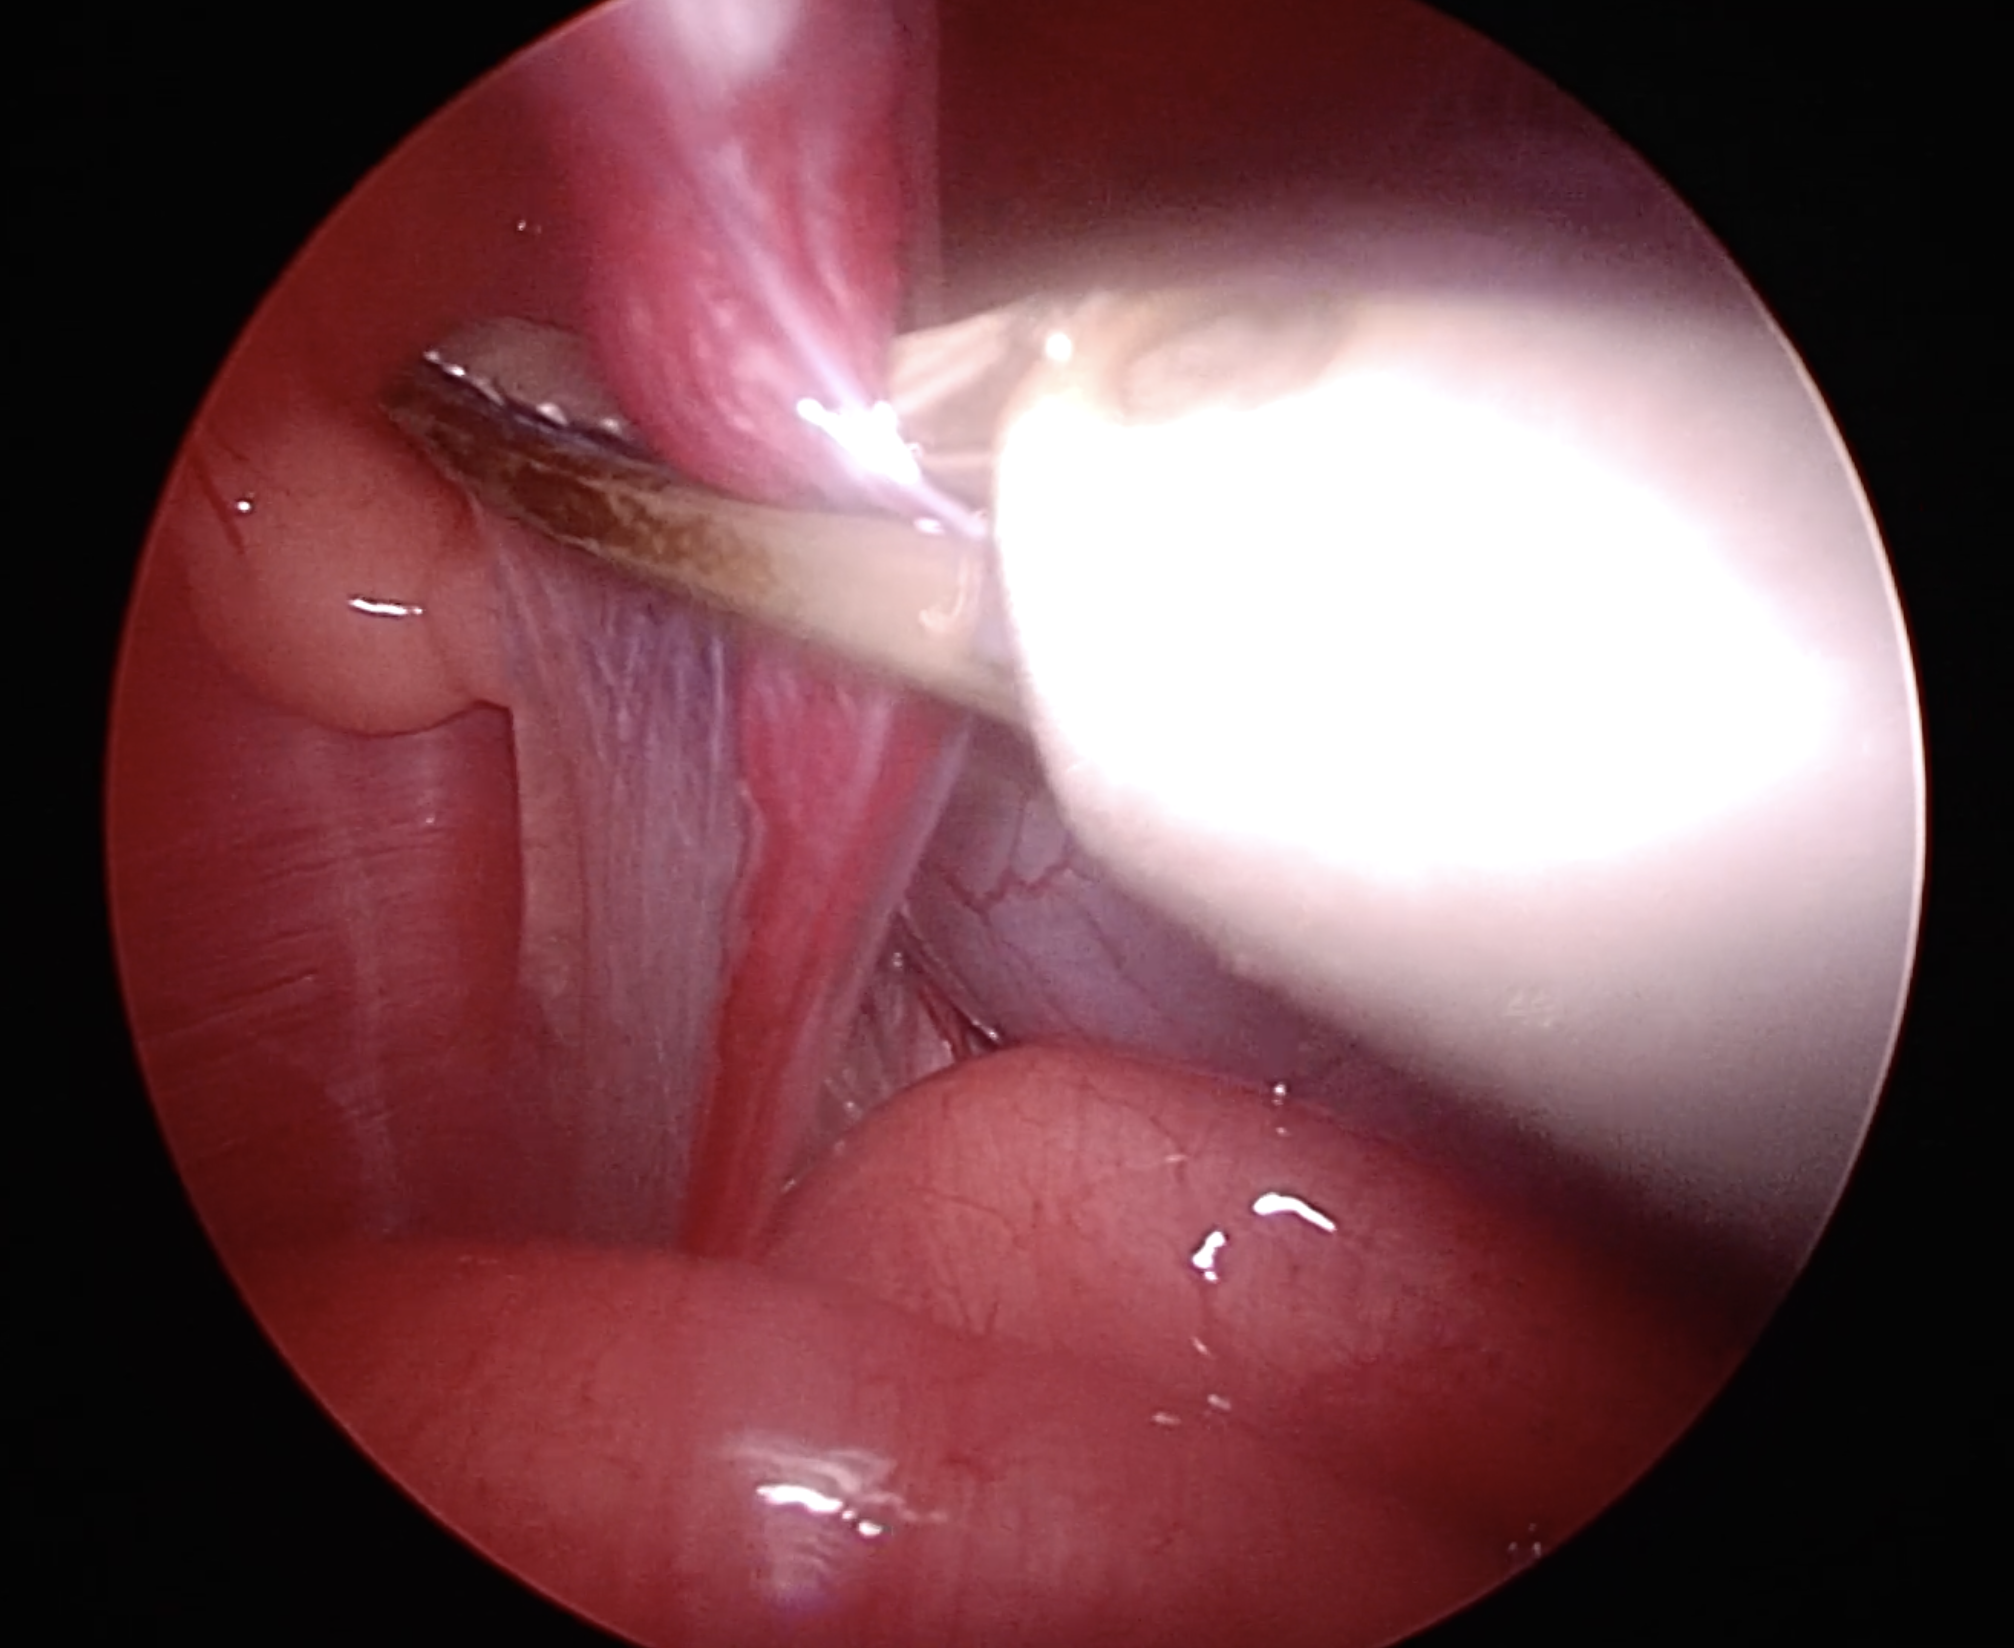

体外に出ずに膀胱の横にとどまっている精巣(右精巣)

左横腹からポートを設置し、精巣をつまみ上げます

右横腹びポートから電気メスのような止血切断デバイスを用いて、精巣の血管を処理、切断します